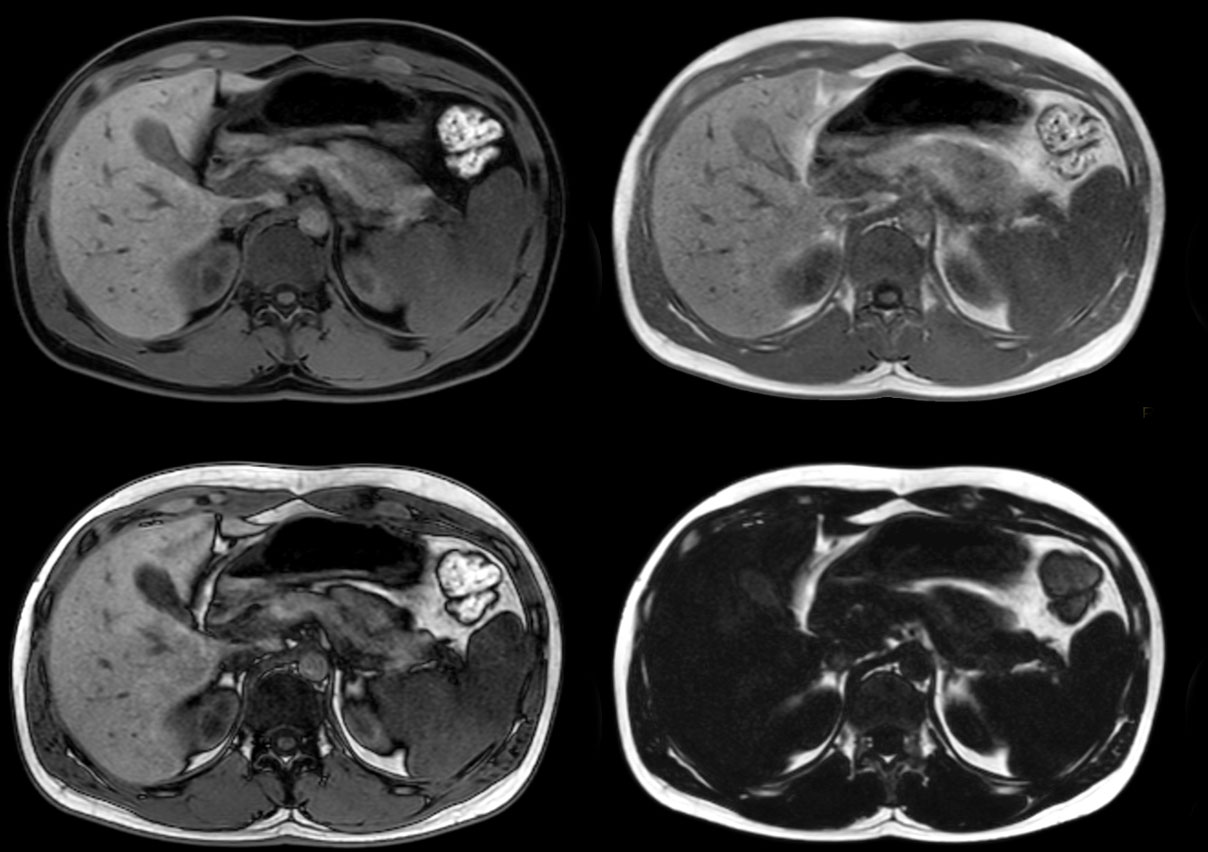

Total torso and liver

• Clinical Application